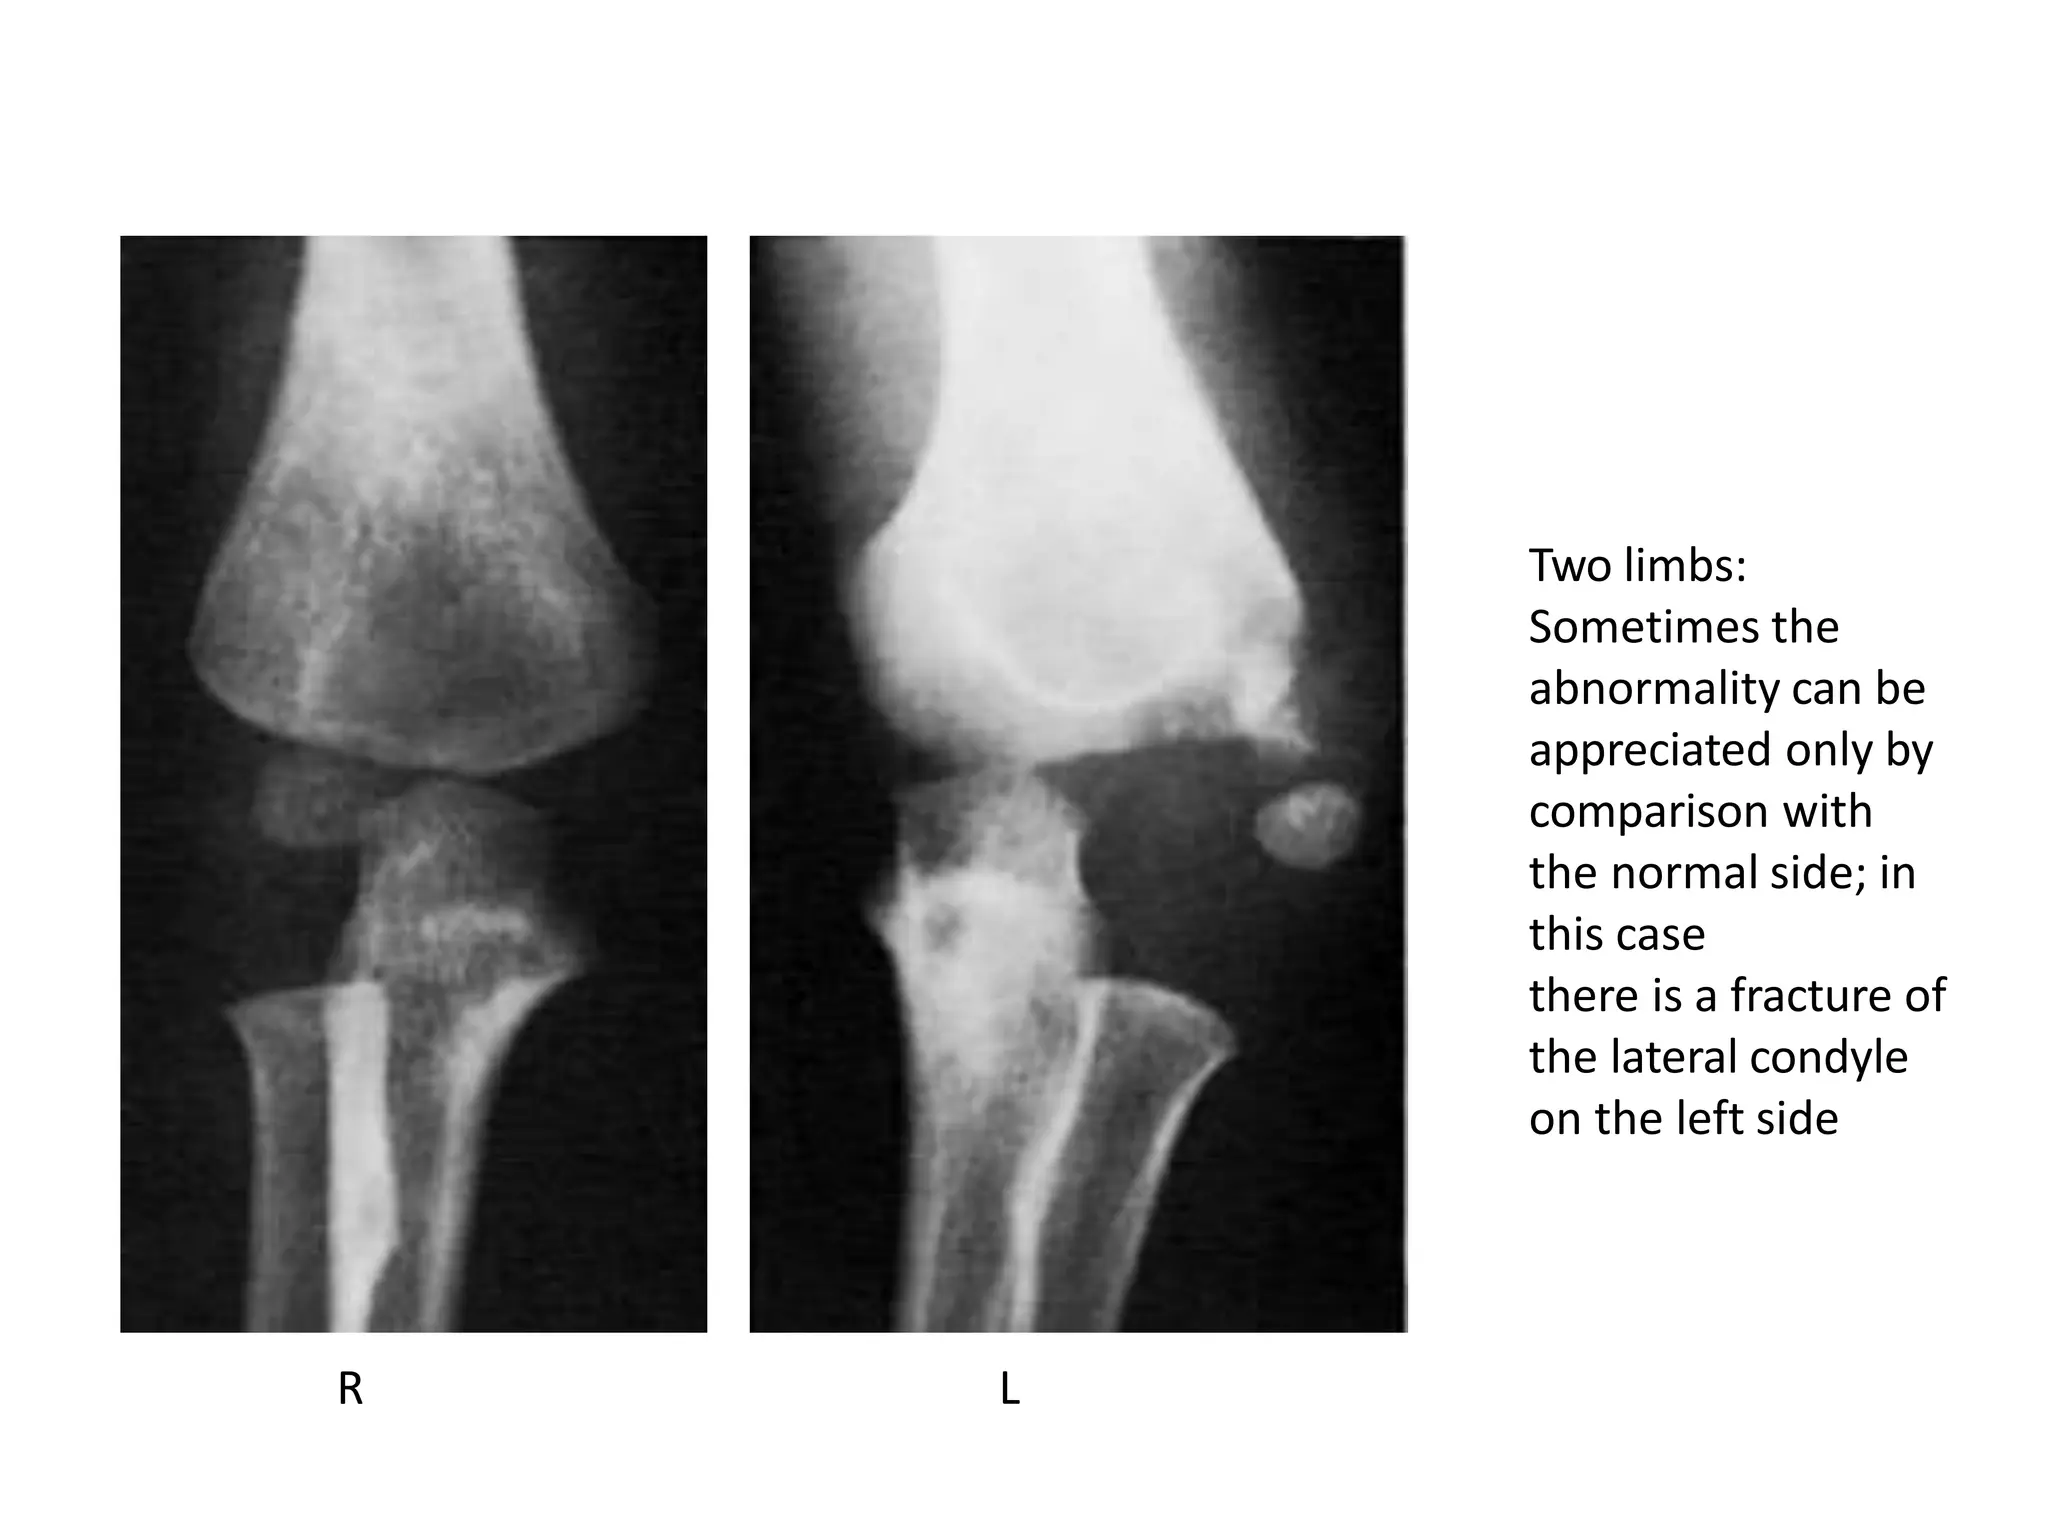

Two limbs – In children, the appearance of immature

rays of the uninjured limb are needed for comparison.

Two limbs:

Sometimes the

abnormality can be

appreciated only by

comparison with

the normal side; in

this case

there is a fracture of

the lateral condyle

on the left side

R L

Two limbs: Sometimes the abnormalitycan be appreciated only by comparison with the normal side; in this case there is a fracture of the lateral condyle on the left side R L